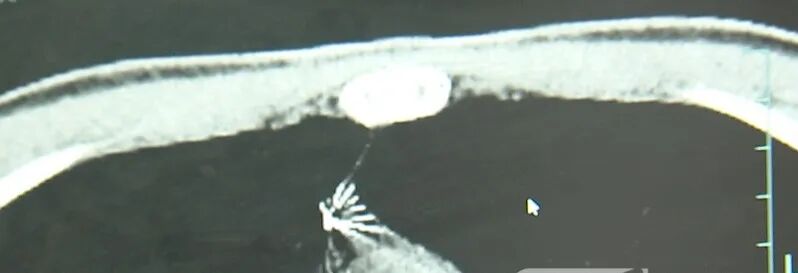

进一步的CT检查确认,异物是一枚金属针,斜插在肺组织内,位置十分凶险。

杭州市第一人民医院心胸外科副主任 冯兴:“我们看到这个针的尖锐部,正好指向他体内的一个大血管,边上是上腔静脉和胸主动脉,因此这个针稍有不慎,就有可能造成周边血管的损伤,甚至危及生命。”